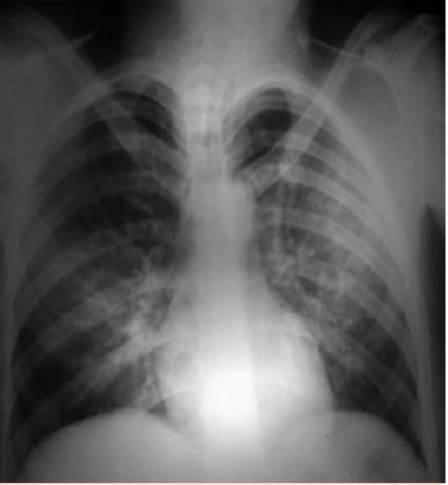

Paciente masculino de 24 años de edad, procedente de área urbana, sin antecedentes patológicos, acudió al servicio de consulta externa de Cirugía del Hospital Regional Santa Teresa, Comayagua, Honduras, con antecedente de dolor abdominal de dos meses de evolución, localizado en el hipocondrio derecho, irradiado a la región escapular ipsilateral, tipo cólico, de intensidad moderada-severa, exacerbado con alimentos grasos, atenuado con analgésicos. Se realizó ultrasonido abdominal que reportó dos litos móviles a la lateralización, con tamaño de 10 x 15 mm en la vesícula, por lo que se ingresó para procedimiento quirúrgico electivo (colecistectomía). Se realizó cirugía dos días después de su ingreso. En el posoperatorio inmediato, quince minutos posextubación, el paciente inició con cuadro clínico de disnea súbita acompañado de hemoptisis, cianosis y alteración del estado de conciencia. Al examen físico se observó Glasgow 13/15, paciente taquipneico (FR = 40 rpm) con evidente dificultad respiratoria, saturación de oxígeno 79%, sin signos de inestabilidad hemodinámica. Mucosa oral húmeda, con restos hemoptoicos; corazón: taquicárdico, sin soplos; a la auscultación pulmonar: abundantes roncus y crepitantes bilaterales, sin áreas de hipoventilación. Los exámenes de laboratorio reportaron leucocitosis, trombocitopenia y acidosis metabólica (Cuadro 1). A su vez, se realizó radiografía posteroanterior de tórax que evidenció infiltrado intersticial bilateral algodonoso, en “alas de mariposa”, característico de edema agudo de pulmón (Figura 1). El tratamiento consistió en apoyo ventilatorio con oxígeno en mascarilla de reservorio a 10 L por minuto, administración de esteroides (metilprednisolona) y diuréticos (furosemida) durante 48 horas con alivio completo del cuadro a las 72 horas del posoperatorio (Figura 2).

Figura 1 Radiografía posteroanterior de tórax, paciente en decúbito supino, se observa infiltrado bilateral intersticial algodonoso, en “alas de mariposa”, característico de edema agudo de pulmón.